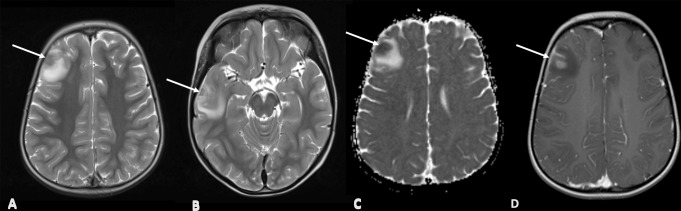

不明原因的神经系统症状可能对先天性免疫错误(IEI)患者的诊断构成挑战,其中病因可能多种多样,不同的病理可能需要不同的治疗方法。脑活检是直接对脑组织进行取样的过程,在历史上提供了组织学和微生物学信息,现在可以用于深层宏基因组下一代分析(mNGS)。我们对2010年至2022年间在英国某三级医疗中心进行脑活检的IEI患儿的临床和诊断数据进行了回顾性分析,其中14例患者符合我们的搜索标准。我们报告了临床特征,不良事件和脑活检的mNGS的额外影响,这些都是进行的。我们发现,在大多数情况下,通过组织或宏基因组学分析,脑活检能够诊断出可控制的并发症(n = 11/14, 79%)。我们发现,mNGS分析提高了29%的IEI病例的脑活检诊断率(n = 4/14)。在71%的病例(n = 10/14)中,脑活检改变了治疗方法。这一系列研究结果为IEI患儿安全且有目的的脑活检提供了强有力的证据。

Unexplained neurological symptoms can pose a diagnostic challenge in patients with inborn errors of immunity (IEI) where the aetiology can be varied, and diverse pathologies may require contrasting treatments. Brain biopsy, the process of sampling brain tissue directly, has historically provided histological and microbiological information and can now be exploited for deep metagenomic next generation analysis (mNGS). We conducted a retrospective analysis of clinical and diagnostic data on paediatric patients with IEI who had a brain biopsy between 2010 and 2022 at a UK tertiary centre where 14 patients fulfilled our search criteria. We report on clinical characteristics, adverse events and the additional impact of mNGS of brain biopsies, where these were conducted. We found that brain biopsy enabled diagnostics with manageable complications in most cases, either by tissue or metagenomics analysis (n = 11/14, 79%). We found that mNGS analysis improved the diagnostic yield of brain biopsy in 29% of IEI cases (n = 4/14). Brain biopsy enabled a change in management in 71% of cases (n = 10/14). This series provides compelling evidence for the safe and purposeful use of brain biopsy in children with IEI.